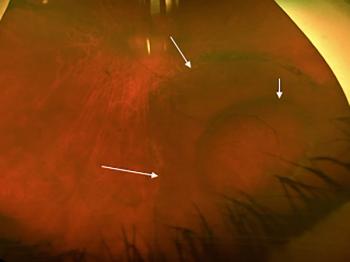

The investigators undertook a study to determine the incidence of rhegmatogenous retinal detachments 1 year after cataract using the IRIS Registry data and to determine the demographic features, ocular comorbidities, and intraoperative factors associated with an increased risk of detachment development.

Patients with a unilateral rhegmatogenous retinal detachment frequently ask about the risk of developing an RRD in their fellow eye.